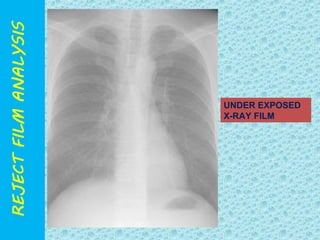

UNDER EXPOSED

X-RAY FILM